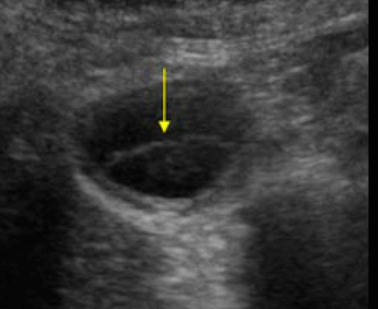

US finding

- 담낭주위 띠모양의 경계가 좋은 액체저류가 보인다

- 담낭은 경계가 불분명해지며 팽팽해진다

- 심한 경우 저에코성 종괴들이 관찰된다